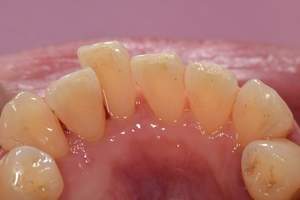

歯石除去

治療前

治療後

| 年齢 | 31歳・女性 |

| 主訴 | 主訴:歯石除去 部位:全顎 |

| 治療内容 | 初診検査・歯石除去 |

| 治療期間 | 2週間 |

| 費用 | 合計:約4,000~5,000円 内訳 初診料:約3,000~4,000円 (保険診療) 歯石除去:約1,000円 (2023年1月現在) |

| リスク・副作用 | ・歯肉の炎症がある場合は歯石除去中に出血を伴う可能性があります。 ・処置後に歯がしみることがあります。 ・歯茎の炎症が軽減すると歯茎が引き締まり、歯が長く見えることがあります。 |

| 治療方針 | 前歯部に叢生(歯列不正)があり多量の歯石が認められました。炎症の抑制を優先するため初診時はTBIのみ行い、2回目以降で歯石除去を行いました。今後は縁下歯石(歯ぐきの中に付着する歯石)の除去を全顎的に行っていく予定です。 |

| 担当者所見 | 叢生(そうせい)とは歯が折り重なるようにデコボコにはえている状態をいいます。歯ブラシが難しく磨き残しをしやすい為、普段使用している歯ブラシに加えワンタフトという細かい部分も磨くことのできる小さな毛束の歯ブラシの使用をおすすめしました。 |

| 担当者所見 | 歯石の存在は感じていたものの歯科医院に苦手意識が強く3年ほど放置していたとのことでした。 舌で触った時にザラザラすることや口臭も気になった為、今回意を決してご来院くださいました。 ブラッシング指導を熱心に聞いてくださり、セルフケアで歯肉の炎症を抑えた上で歯石除去ができたのでお痛みが少なく行えました。 患者様も苦手意識が克服できたと喜んでくださり、今後の治療にも積極的な姿勢です。 |